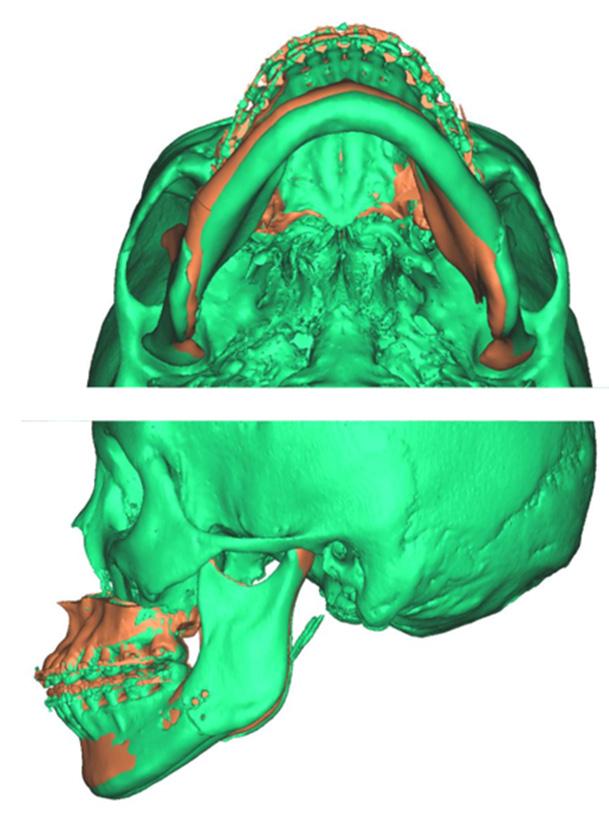

2. Superimposed digital reconstruction skull images from Materialise Magics with the planned final outcome in orange and the post-operative scan data in green